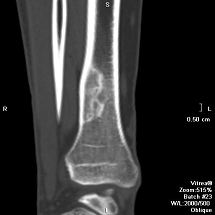

Костно-суставная система

КТ является эффективным методом оценки состояния

крупных плоских и длинных трубчатых костей, превосходящим по своим возможностям

базовую рентгенодиагностику. Оценка состояния суставов в целях онкологической

диагностики с помощью КТ также эффективна, а для других целей, как правило,

используется МРТ. Мелкие и тонкие кости исследуются с техническими трудностями

и с меньшей результативностью.

В диагностике первичных костных опухолей КТ

позволяет получить изображения не только эндооссального (внутрикостного)

компонента и периоста, но и экзооссального (внекостного) мягкотканного

компонента опухоли. В некоторых случаях обнаружение внешнего компонента имеет

решающее значение в дифференциальной диагностике опухолевой, диспластической и

воспалительной патологий. Проще, чем при базовой рентгенодиагностике,

происходит оценка остеолитических (результат деятельности клеток-остеокластов)

и остеобласти-ческих (последствия работы остеобластов) изменений, особенно при

их сочетании. В диагностике опухолей мягких тканей немаловажным преимуществом

КТ является возможность определения их взаимоотношений с костями и суставами. В

обоих случаях приобретается ценная информация о границах распространения

опухоли и ее контакте с другими анатомическими структурами. В диагностике

метастазов действуют те же принципы, что и в исследованиях первичных опухолей.

КТ костно-суставной системы